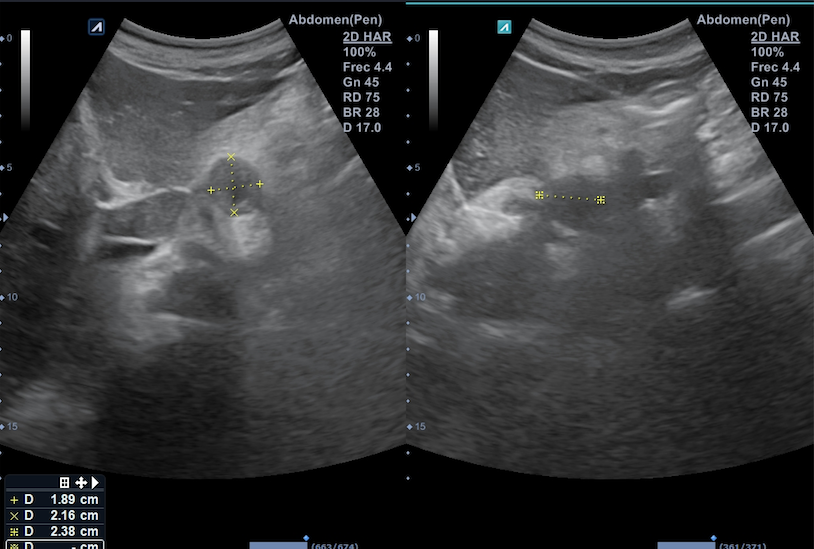

Citamos en consulta para realizar ecografía abdominal destacando a la exploración la presencia de 3 formaciones en retroperitoneo superior, en zona subdiafragmática y mediales al hiato aórtico: la primera a la derecha del tronco celiaco, de aspecto ovalado e isoecogénico de 1,2 x 1,9 cm; la segunda en línea media, debajo del lóbulo caudado, de aspecto hipoecogénico y con zona central de menor densidad de 1,9 x 2,2 cm; la tercera, a la izquierda de esta última de 2,2 x 2,8 cm sugerentes de adenopatías retroperitoneales.